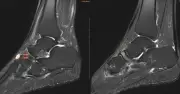

Một nữ giáo viên 52 tuổi được chẩn đoán mắc Hội chứng Mueller-Weiss, bệnh hoại tử xương hiếm với tỷ lệ dưới 1/1.000.000 dân. Bác sĩ cảnh báo thói quen đứng lâu, chạy bộ có thể gây vi chấn thương dẫn đến bệnh lý nguy hiểm này.